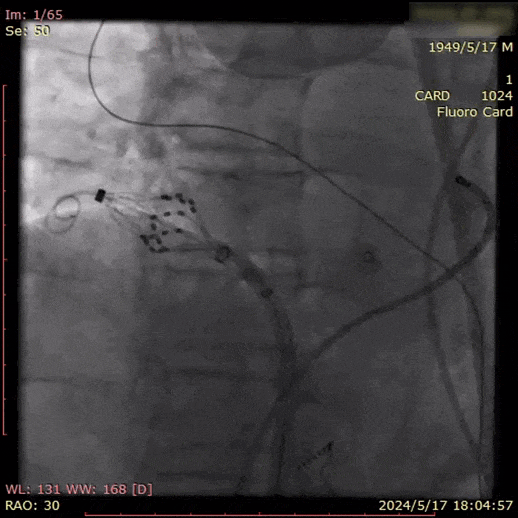

房间隔穿刺后,沿可调弯鞘管将脉冲消融导管送入左房内,测量基线阻抗后,依次将脉冲消融导管送入左上肺静脉、左下肺静脉、右上肺静脉、右下肺静脉四个肺静脉口部与前庭实施脉冲电场消融。

消融完成后,使用三维进行基质标测,验证肺静脉隔离符合消融终点。X线透视确认心包正常。手术顺利结束,患者安返病房。

LSPV消融

消融导管呈网篮与花瓣形态下放电。

LSPV和LIPV之间补充消融

常规肺静脉前庭消融

共干肺静脉前庭消融

左肺完成肺静脉口部消融后,将导管撤至前庭处,打成花瓣状,由上而下分别覆盖前庭位置,实现前庭充分隔离。

RSPV消融

RIPV消融

RSPV和RIPV之间补充消融

两肺间补充消融

右肺常规完成肺静脉口部和前庭消融后,在上肺前庭下压导管,下肺前庭上送导管,实现两肺间充分隔离。